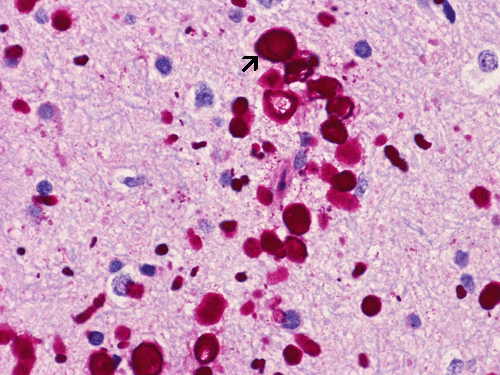

Polyglucosan body disease, PAS stain: The polyglucosan bodies (arrow) are strongly positive for PAS stain due to their high content of polysaccharide. These polysaccharides are diastase resistant and therefore polyglucosan bodies are also visualized with PAS stain with diastase pretreatment. Note that the is a spectrum of different sizes of polyglucosan bodies in this image.